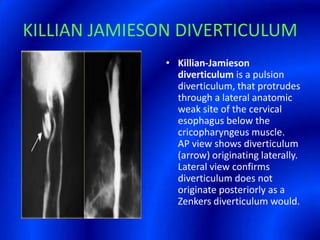

This document provides information about a barium swallow procedure. It begins with an introduction and overview of the embryology and anatomy of the pharynx and esophagus. It then describes the procedure itself, including preparation, technique, views obtained, and indications. Specific conditions that may be examined include pharyngeal and esophageal webs, foreign body impaction, scleroderma, dysphagia, mediastinal masses, and carcinoma. Diagrams are provided to illustrate normal anatomy and various pathological findings.